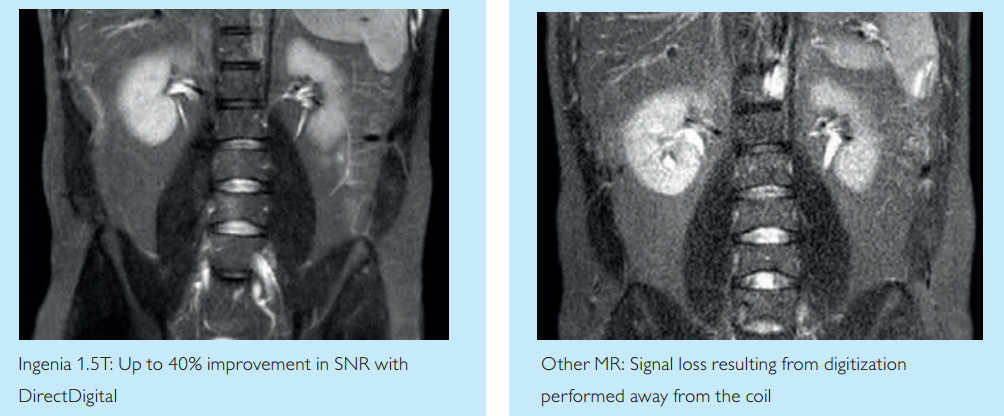

該設備在實現了數字線圈、數字接口與全程數字傳輸,突破傳統磁共振模拟信号源的瓶頸,保證獲得(de)原始圖像信号無損真實還(hái)原的基礎上,加載先進的數字網絡控制系統,從(cóng)而控制射頻、梯度、重建各核心部件(jiàn)實時同步、精準協作(zuò),還(hái)原影(yǐng)像本真,實現圖像的精準定量。

1、全面提升臨床科研應用,圖像信噪比提升40%;掃描時可(kě)發現1毫米以下的腫瘤,達到早期診斷和早期治療的目的。